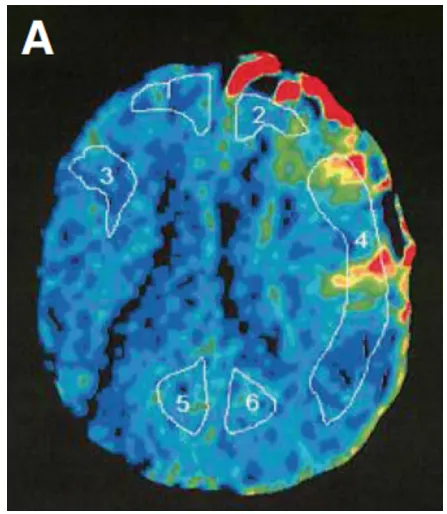

幸子需要早期手术血运重建,但甲状腺毒症被认为是手术的。开始强化甲状腺激素治疗,大约70天后达到激素缓解(图2A)。进行左侧STA-MCA搭桥术。由于术后不久观察到左MCA区域的高血流灌注现象(图3A),因此给予巴比妥酸盐昏迷治疗3天。术后未发生额外的缺血性和出血性并发症(图2B,C)。入院时神经功能缺损MRS评分为4分、重度残疾标准,术后3个月时恢复2分轻度残疾,无需协助下可以完成日常起居之事。

▼图3:A,术后Xe-CT显示左侧大脑中动脉区域明显血流灌注(局部脑血流量:26.8 ml/100 g/min),血管通畅。